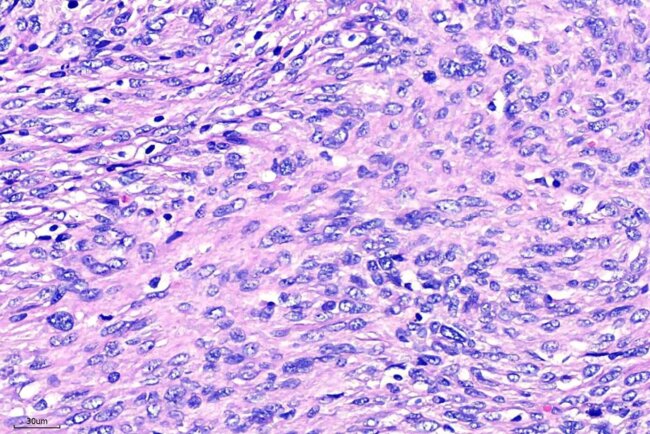

犬傳染性花柳性腫瘤(Canine Transmissible Venereal Tumor, CTVT)

血管壁周圍細胞瘤(Perivascular wall tumor, PWT)

Toluidine blue染色

動物外科病理-腫瘤淋巴結轉移

腫瘤轉移-腎臟 Tumor renal metastases